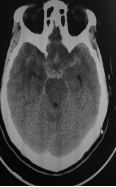

3天前无明显诱因突发剧烈头痛、恶心呕吐,神志清于2018年8月16日由外院转入青岛大学附属医院,CT示鞍上池中等量出血,以右侧侧裂池出血明显多。DSA和CTA示右侧ICA内侧壁有类圆形的囊状膨出,术前考虑为血泡样动脉瘤,术前Hunt-Hess分级II级。